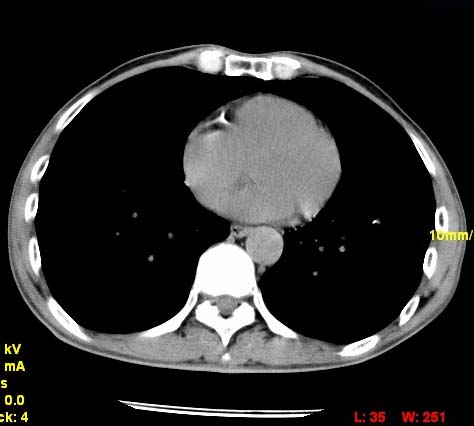

以下是引用wangzhengyuan在2007-11-11 23:31:00的发言:[br]钙化灶,看上去不像转移。

以下是引用zjzjr在2007-11-12 8:35:00的发言:[br]考虑错构瘤,建议定期复查.

以下是引用卜一在2007-11-12 5:59:00的发言:[br]病灶本身不像转移,不知有没有以前的胸部ct片,若有,则可以对比以下,若是新出现病灶,应高度警惕“转移”的可能![br]